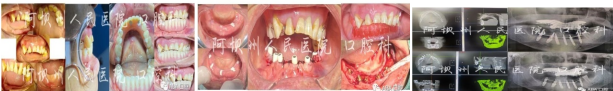

完美蜕变,术前术后对比。

2023年7月10日上午10时开始,蔡炜老师带领大家为患者精细设计、精细手术、精诚讲解,手术历时2小时余,拍片见植入位置均非常理想。

中午12:30开始,来自爱美工作室的邬丽老师为患者取模、制作即刻修复义齿,经过约3小时的设计及制作,完美戴入患者口内。